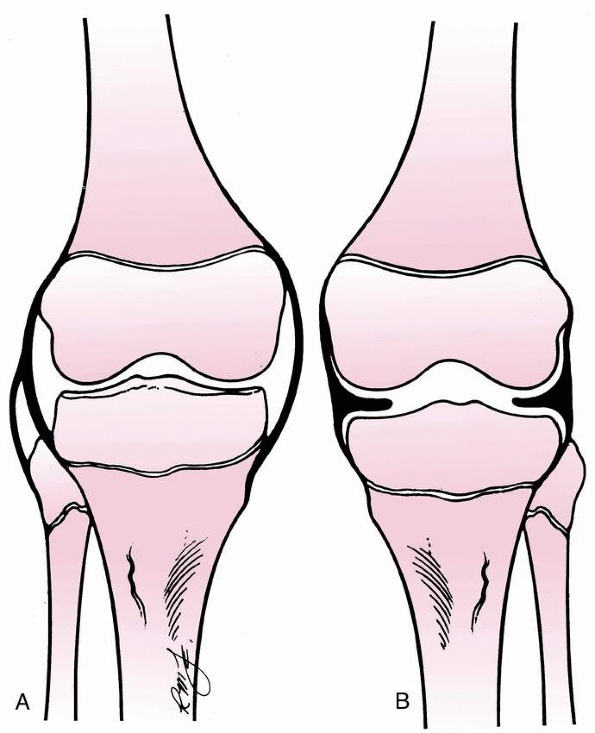

FIGURE 24-2 Classification of tibial spine fractures. A. Type I, minimal displacement. B. Type II, hinged posteriorly. C. Type III, complete separation.

-

Type 1—minimal displacement of the fragment from the rest of the proximal tibial epiphysis

Type 2—displacement of the anterior third

to half of the avulsed fragment, which is lifted upward but remains

hinged on its posterior border in contact with the proximal tibial

epiphysis -

Type 3—complete separation of the avulsed fragment from the proximal tibial epiphysis, with upward displacement and rotation

The interobserver reliability between type 1 and type 2/3 fractures is

good; however, differentiation between type 2 and 3 fractures may be

difficult.175